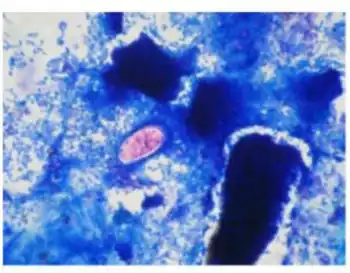

strained oocyst of Cystoisospora belli | |

A fully mature (sporulated) oocyst of genus Isospora is a spindle-shaped body that has two sporocysts that contain four sporozoites each.[4]

The oocysts of Cystoisospora belli are long and oval shaped. They measure between 20 and 33 micrometers in length and between 10 and 19 micrometers wide.[5]